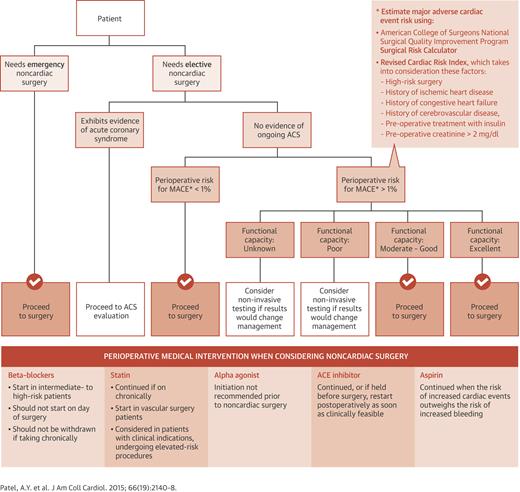

Khonsari's Cardiac Surgery: Safeguards and Pitfalls in。Khonsari's Cardiac Surgery: Safeguards and Pitfalls in。Atlas of Cardiac Surgical Techniques: A Volume in the。天草産しらぬい 家庭用 箱込2kg。Efk5_mO5bzht0D-。ACHDのカテーテル治療:現在まで,そして未来へ。心臓血管外科手術のまずはここから | 岡本 一真 |本 | 通販 | Amazon。\r裁断した状態のため「全体的に状態が悪い」にしています。Outcome benefits of surgical ablation and left atrial。3月3日、循環器内科と心臓血管外科の医師の下、新たなEV-ICD。Abtin H. Khosravi, MD | Orange, CA。非心臓手術時の心臓リスク」管理のための10のポイント:JACC誌。新品購入したものを裁断しています。\r自炊用に裁断したバラバラ状態のため普通には読めません。Now Offering Telehealth Visits | Coastal Heart Medical Group。代表的な手術法 その工夫と問題点。\rご理解のある方のみご購入をお願いします。定価 25000円#裁断済み#自炊用#医学書